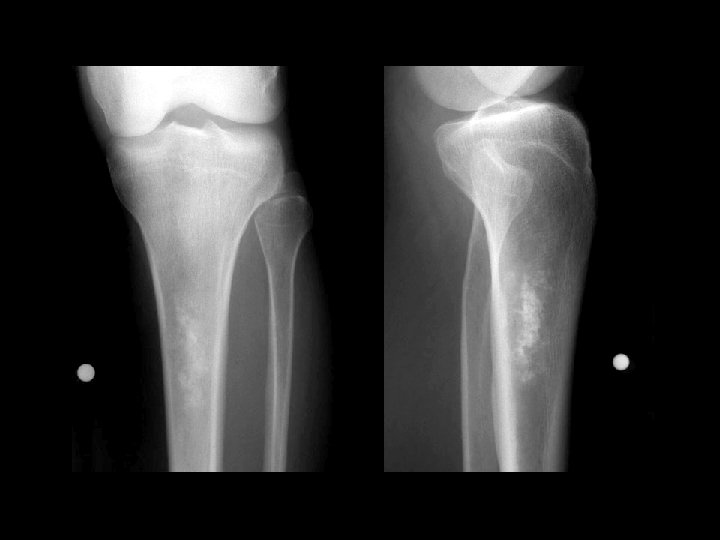

Melorheostosis • • • Findings: – Peripheral hyperostosis of the tibia producing a wavy sclerotic diaphyseal contour Rare bone disorder of childhood “candle wax” dripping down the bone appearance presents with PAIN and joint swelling ddx: – Paget’s – myelofibrosis – renal osteodystrophy – sclerotic mets

Aneurysmal bone cyst • Findings: – Lucent end of bone lesion in the proximal tibia – Slightly expansile, mild periosteal reaction – Fluid-fluid level on MRI • ddx: – Giant cell tumor – Unicameral bone cyst – Fibrous dysplasia – Chondroblastoma (rare)

Enchondroma • Findings: – Patchy sclerotic intramedullay lesion in the proximal tibial metadiaphysis – “Rings and arcs” calcification • ddx: – Bone infarct